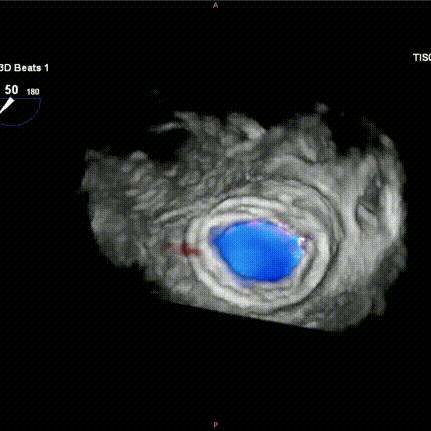

图H-I:瓣膜释放后食道超声检查提示瓣膜位置稳定,功能良好,且无瓣周漏发生。

6.术中左心室造影即刻显示Mi-thos生物瓣膜位置良好、形态理想,未见瓣内反流、瓣周漏(PVL)或左心室流出道梗阻(LVOTO)现象(新生左心室流出道面积为 374.6 cm²);TEE进一步评估瓣膜位置及功能,显示平均跨瓣压差为3 mmHg。